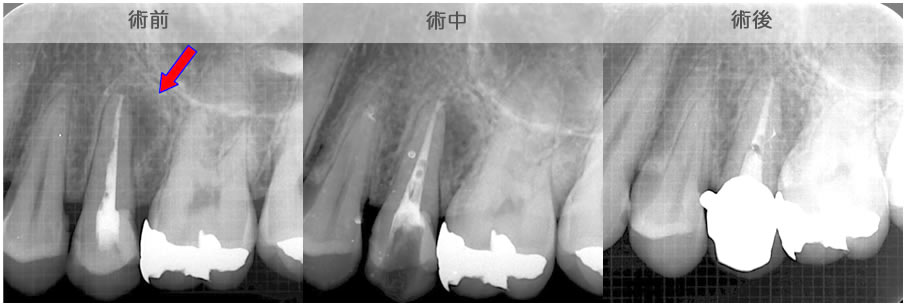

頬側骨壁の根尖部まで無くなっています。

MTA根充後11ヶ月で透過像が消失し、根尖部が正常化しました。

頬側骨の喪失が見られましたが17ヶ月で回復しました。

頬側骨の回復が確認できます。

| 治療説明 | 左下第一小臼歯の頬側根尖部からの排膿、痛みはないそうです。X線画像では根尖部に透過像を認められます。 頬側の骨も失われており、歯髄が死んだことが原因と考えられます。修復物を除去後根管治療を行い、根管充填後、透過像は消失、頬側骨も再生されていました。 |

|---|---|

| 治療期間 | 6〜24ヶ月 |

| 治療費用 | 150,000〜300,000円 |

| 治療に伴うリスク | 根管内からの治療で根尖病巣が治らない場合は、外科的に根尖病巣を除去する必要があります。 再根管治療を繰り返す場合、歯根の厚みが薄くなり、歯根破折のリスクが高まります。 |